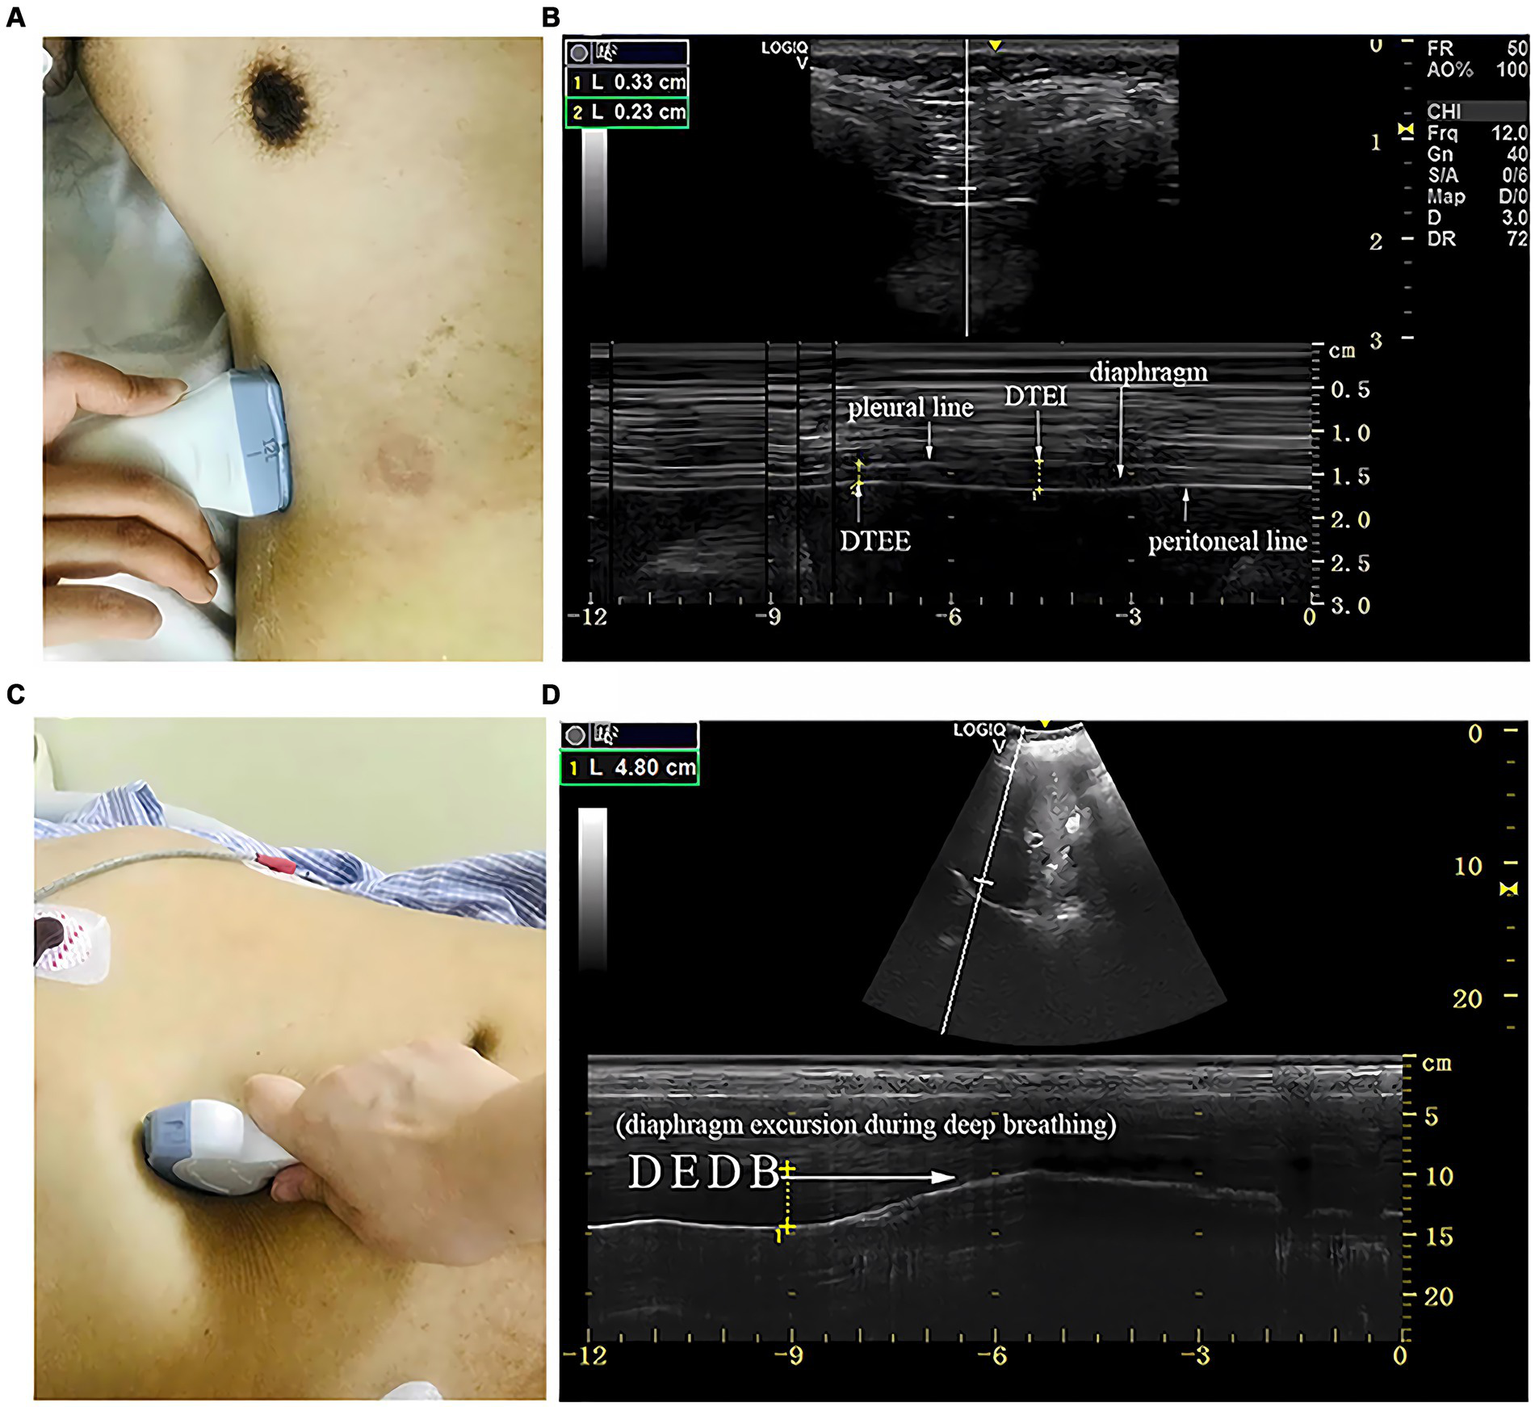

Measurements of DT and DTF require the use of a high-frequency linear ultrasound transducer (3–12 MHz). The patient should be in a semi-recumbent position, and the probe should be placed in the midaxillary line at ribs 8–10, perpendicular to the intercostal space. In B-Mode, the diaphragm can be visualized as a three-layered structure, with the upper hyperechoic layer being the pleura, the lower layer being the peritoneum, and the middle layer being the diaphragm (29) (Figures 2A,B). In contrast, DE measurements are performed using a low-frequency abdominal convex probe (3–5 MHz), the patient should be positioned at a 45-degree semi-recumbent angle, and the ultrasound probe should be placed parallel to the right costal margin at the right midclavicular line, using the transverse section of the liver as an acoustic window. Alternatively, the probe can be placed perpendicular to the costal margin to obtain a longitudinal section of the liver (Figures 2C,D). It is also possible to obtain diaphragm images at different interfaces using liver vessels as markers, however, this method is not commonly used (Figure 3). In B-Mode, the high echo shadow covering the liver surface represents the diaphragm, switching to M-Mode allows for the observation of the diaphragm waveform synchronized with the respiratory cycle (Figure 4B). On the left side, the probe is placed at the 8–10th rib along the midaxillary line, parallel to the intercostal spaces, the other methods are the same as for the right side (Figure 4A) (29). Ultimately, ultrasound is clinically reproducible (32) and has become an essential tool for most clinicians, its overall measurement failure rate has decreased from 27% a decade ago to 0.7% today, demonstrating the effectiveness of ultrasound technology (33).

Figure 2

The measurement of diaphragmatic thickness and excursion. (A) A 10–15 MHz probe was placed at the zone of apposition. (B) The non-echogenic layer between the yellow markers indicates the thickness of the diaphragm at the end of expiration and inspiration. (C) A 2–5 MHz curved-array probe was placed under the costal margin. (D) The bright line indicates diaphragmatic excursion during deep breathing. DTEE, diaphragm thickness at end-expiratory; DTEI, diaphragm thickness at end-inspiration; DEDB, diaphragmatic excursion during deep breathing (30).